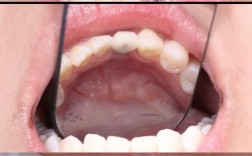

唇腭裂患者的口腔颌面特点具有复杂性,其畸形程度可分为单侧完全性唇腭裂、双侧完全性唇腭裂、不完全性唇腭裂等多种类型,不同类型的畸形表现差异较大,典型问题包括:牙弓狭窄呈“V”形,上颌骨发育不足导致面中部凹陷,牙齿萌出位置异常(如腭侧萌出、颊侧萌出),牙列拥挤或稀疏,前牙反颌(俗称“地包天”),后牙反颌及锁颌,以及因裂隙存在导致的缺牙或多生牙等,这些问题不仅影响咀嚼、发音功能,还会对患儿的心理发育造成负面影响,因此早期干预和系统性正畸治疗至关重要。

唇腭裂正畸治疗面临诸多挑战,其中上颌骨发育不足是最常见的问题,表现为面中部凹陷、前牙反颌,需通过前方牵引、面具式矫治器等骨性矫形技术刺激上颌骨生长;牙弓狭窄易导致后牙反颌,需快速扩弓或慢速扩弓技术改善牙弓宽度;裂隙区牙齿萌出异常可能需要外科手术助萌或正畸牵引;患儿配合度、瘢痕组织对牙齿移动的影响、治疗后复发风险等也是治疗中需重点关注的问题,应对措施包括:加强医患沟通,提高患儿配合度;多学科协作(正畸科、整形外科、语音治疗科等)制定综合方案;采用支抗增强技术(如种植支抗)确保牙齿移动的精准性;治疗后长期佩戴保持器,定期复查以维持疗效。